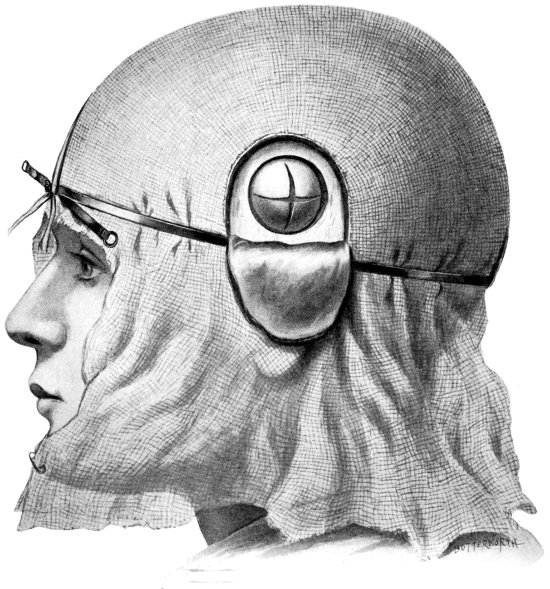

Fig. 4. The Scalp-tourniquet. Front View.

Fig. 5. The Scalp-tourniquet. Back View.

All surgeons must have appreciated the difficulty attendant on the application of forceps to, and the ligature of, divided scalp-vessels. The patient may lose a considerable quantity of blood, and much valuable time will be wasted before the more essential part of the operation is commenced. All this can, under ordinary circumstances, be avoided by the use of the scalp-tourniquet. As used by Cushing it consists of a rubber ring fashioned after the style of an Esmarch’s tourniquet, encircling the head and passing from the lower frontal region in front, above the ears, to the lower occipital region behind. A median tape, passing from glabella to occiput, prevents any tendency for the tourniquet to slip down over the eyes, at the same time acting as a convenient landmark for the superior longitudinal sinus.

I found Cushing’s tourniquet rather inconvenient in its application, and, after various modifications, am accustomed to use the one depicted in the illustration. It consists of two flat metal bands connected posteriorly by a strong rubber connecting link, the two bands passing in front through a metal fixation piece possessing a screw which, when tightened up, allows of the maintenance of the desired pressure. The median tape, previously mentioned, helps to keep the tourniquet in position.

The tourniquet is applied as follows: the whole head is enveloped in gauze—two or three layers thick, and cut to the size and shape of a large handkerchief. The tourniquet is slipped over the head,[16] as low down as possible, and then tightened up. The median tape, having a loop behind through which the tourniquet passes, is laid in the middle line and tied round the screw on the fixation piece.

The gauze should then be moistened with saline solution or some mild antiseptic, so that it clings tightly to the underlying scalp and becomes sufficiently translucent to allow of the recognition of any underlying landmarks that may have been previously mapped out with the scalpel, iodine, silver nitrate, or aniline pencil.

The scalp-flap is then framed by incisions carried down to the bone, through gauze and scalp, in one sweep. The flap is turned down and covered with gauze. By the adoption of this method hæmorrhage from scalp-vessels is efficiently controlled and the risk of wound infection is reduced to a minimum.